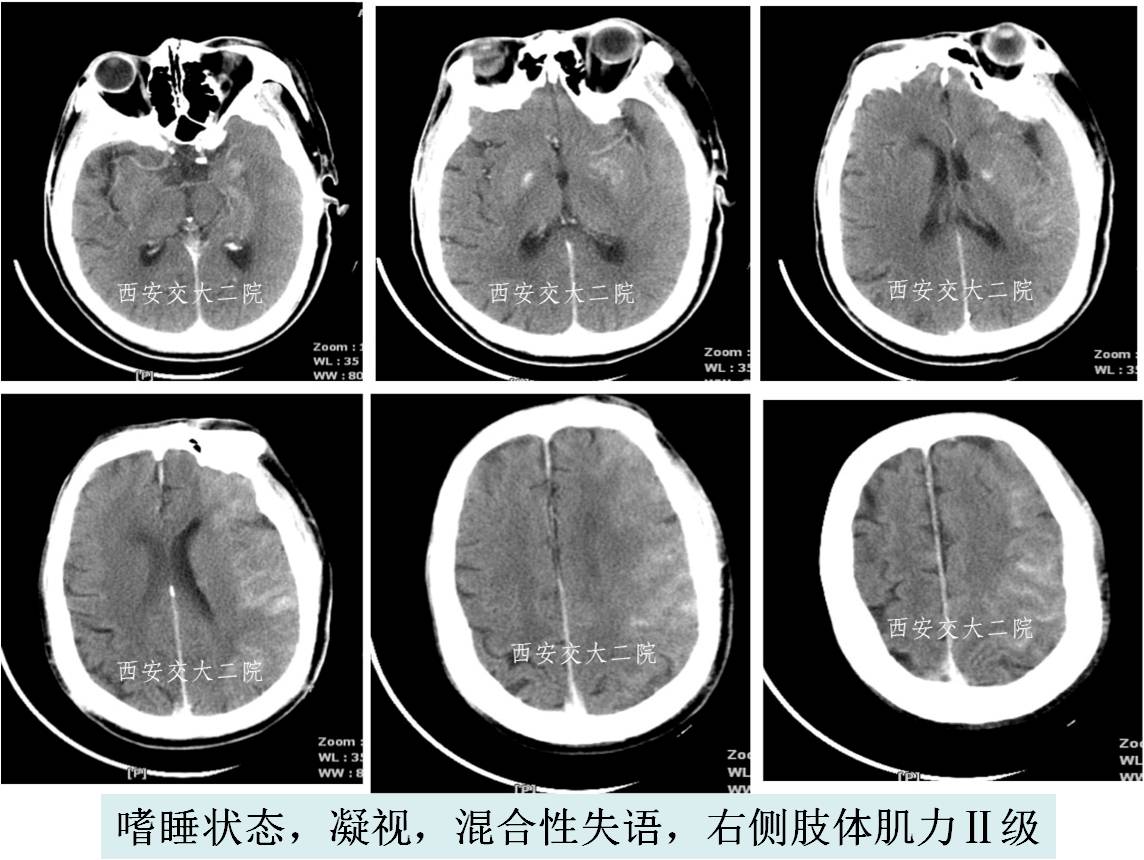

》查体:嗜睡,混合性失语,双眼向左凝视,双侧瞳孔形圆等大,直径约3mm,对光反射灵敏,右侧肢体肌力0级。

急诊脑CT

初步诊断

1. 脑栓塞 (左侧大脑中动脉闭塞)?

病后2小时DSA示左颈内动脉眼段闭塞。

取栓后即刻脑CT及临表

术后24h脑CT及临表

术后4天脑CT及临表

术后2周脑CT及临表